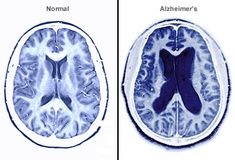

अल्जाइमर रोग के जोखिम को कम करने में आहार की महत्वपूर्ण भूमिका: अध्ययन

शोधकर्ताओं ने पहचान की है कि अल्जाइमर रोग के विकास के जोखिम को कम करने में कौन से आहार प्रभावी हैं।